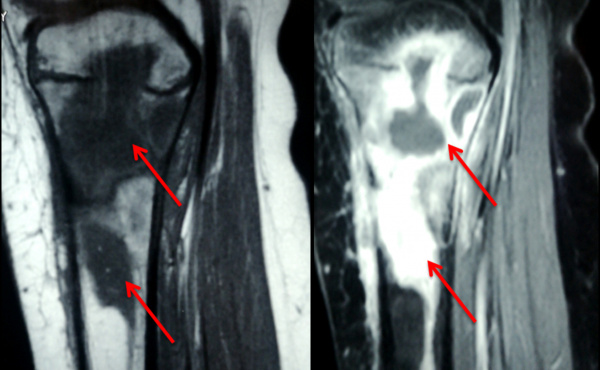

МРТ коленного сустава. Остит и остеомиелит проксимального отдела большеберцовой кости (красные стрелки)